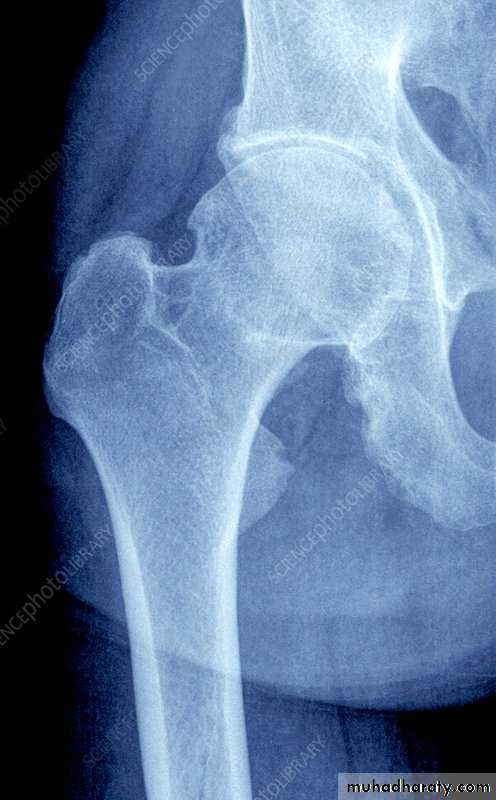

Up to 40% of patients also have peripheral musculoskeletal lesions (asymmetrical, affecting entheses of large joints, such as the hips, knees, ankles and shoulders).

Erosive changes may be seen in the symphysis pubis, ischial tuberosities and peripheral joints.

Severe hip, knee or shoulder arthritis with secondary OA may require arthroplasty.